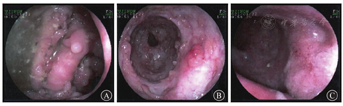

入院后予以美沙拉秦缓释颗粒(2 g/次,2次/d)抗炎、中/长链脂肪乳注射液(250 mL/d)+混合糖电解质注射液(500 mL/d)+复合磷酸氢钾注射液(2 mL)等营养支持治疗;患者外院抗感染、抗病毒、糖皮质激素治疗数月,腹泻、脓血便症状明显改善,但每次糖皮质激素减量后,症状出现反复,考虑为糖皮质激素依赖,遂转换为生物制剂治疗。经与患者沟通、协商后,于2020年9月28日予以IFX治疗,患者体重为58 kg,治疗剂量为300 mg/次。患者腹泻、便血较前好转,遂出院,出院后继续口服醋酸泼尼松(早餐后口服,20 mg/次;晚餐后口服,10 mg/次),每2周减量5 mg,减量至20 mg/d时每2周减量2.5 mg。2020年10月22日患者进行第2次IFX 300 mg治疗;11月25日,因患者体重上升至66 kg,调整IFX剂量至400 mg。经3次IFX治疗后,患者腹泻、便血症状较前明显缓解,排便频率为2~3次/d,粪便性状为黄色成形软便。2021年1月,醋酸泼尼松减量至7.5 mg后患者开始间断出现腹痛、便血症状,于1月22日至空军军医大学西京医院消化内科复诊,查IFX血药浓度为1.0 μg/mL,抗IFX抗体浓度<4 ng/mL,肠镜检查(图6)示升结肠至乙状结肠见散在瘢痕,并见多发丘状或结节样、团块状隆起,黏膜粗糙,散在糜烂、溃疡,肠腔多段狭窄,镜身尚可通过;直肠散在点片状黏膜充血、糜烂,表面覆白苔,血管纹理模糊。肠镜检查结果较前好转,部分呈瘢痕愈合,降结肠狭窄较前改善。患者此次症状反复,考虑与IFX血药浓度较低有关,遂于2021年1月25日优化IFX剂量至500 mg治疗。因个人原因治疗时间延迟6周后,2021年5月14日患者于空军军医大学西京医院完成第5次IFX 500 mg治疗。2021年8月20日于当地医院完成第6次IFX 500 mg治疗。2021年9月电话随访,患者腹痛、腹泻、便血等症状较前明显缓解,排便频率为1~3次/d,无黏液脓血便,间断偶有腹痛,可耐受。